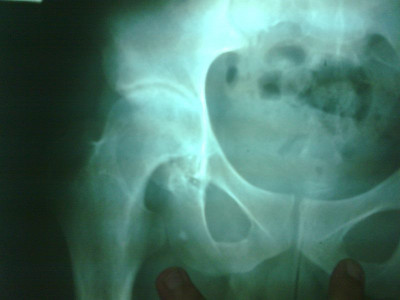

Radiografías con enfoque en fisiatría

Envíado por Dr. Hernán Darío Sánchez Ramos